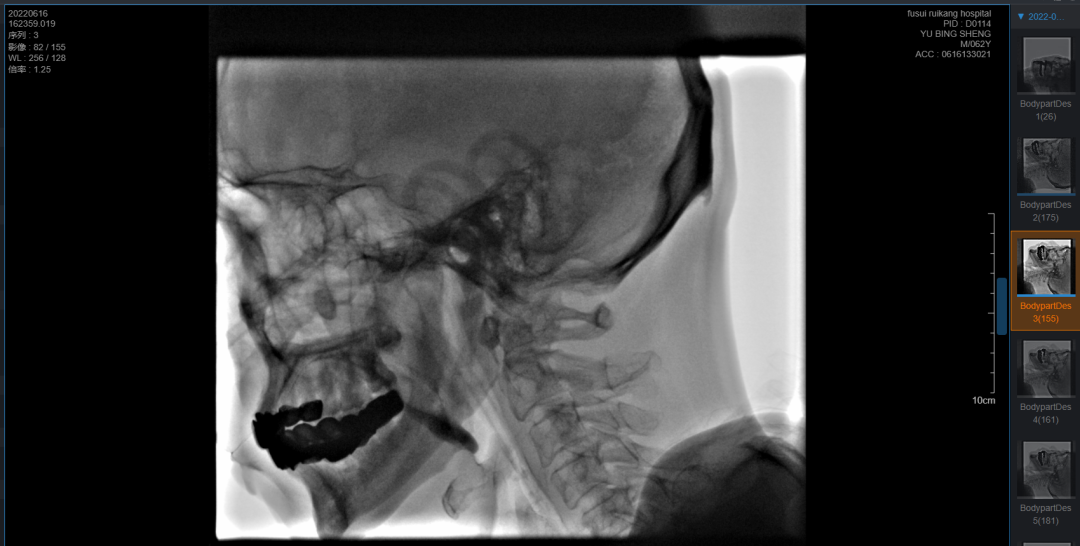

视频透视吞咽检查(VFSS) 吞咽造影

1)即X线透视下,对口 咽 喉 食管的吞咽运动进行的特殊造影。

2)可用于协助诊治吞咽障碍,被视为吞咽障碍检查的理想方法和诊断的金标准